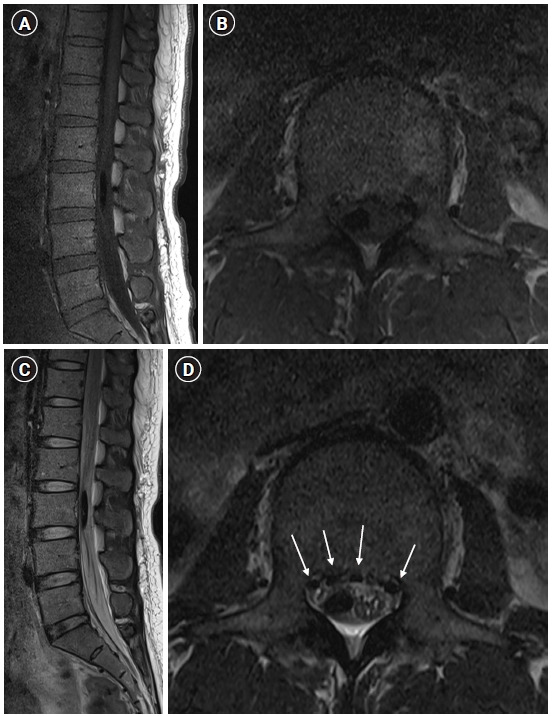

Cases: A 41-year-old pregnant woman was scheduled to undergo epidural anesthesia for cesarean section. After attempting epidural anesthesia, she experienced prolonged hypotension and recovery time, especially in the right extremity. Through magnetic resonance imaging we found subdural air bubbles compressing the right side of the cauda equina in the L3 region. Thus, we considered unintended subdural anesthesia and performed conservative management with close observation. Her symptoms completely resolved within 24 h.